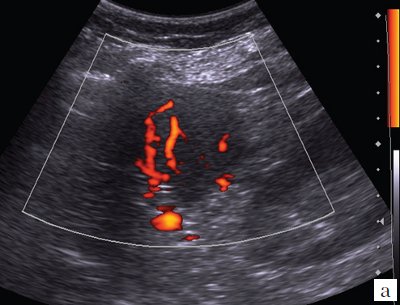

При дуплексном сканировании в структуре образования определяются сосуды (рис. 5, а): регистрируются артерии (линейная скорость кровотока - ЛСК - от 0,33 до 0,47 м/с) и вены (ЛСК от 0,08 до 0,12 м/с) (см. рис. 5, б). Вокруг образования отмечается некоторое обеднение сосудистого рисунка, наиболее вероятно, за счет компрессии окружающей ткани селезенки.

Рис. 5. Дуплексное сканирование гамартомы селезенки.

а) Режим энергетического допплера.